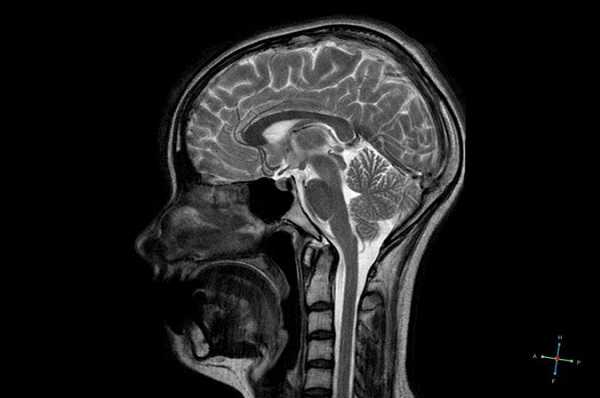

Снимок МРТ головного мозга в двух проекциях

Гипофиз на снимке МРТ

МРТ гипофиза в норме